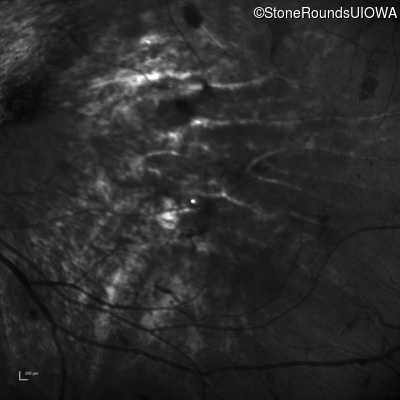

Infrared Fundus Photograph - Right - 20/200 -1

Exemplar

Infrared Fundus Photograph - Left - 5/160